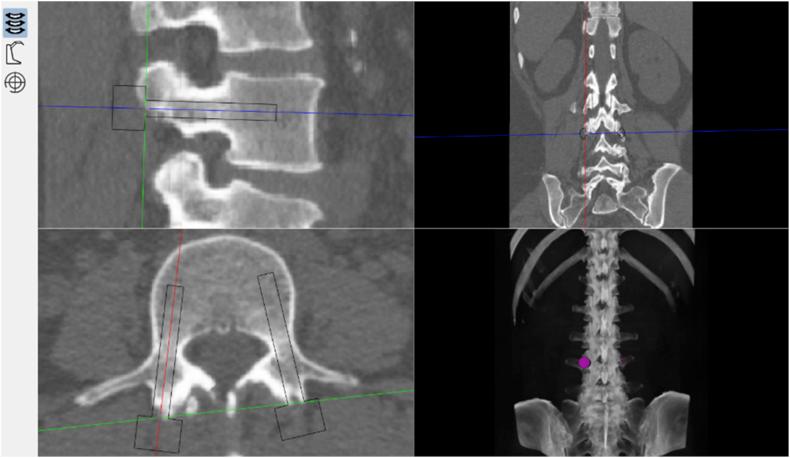

Existing orthopaedic robotic systems are almost restricted to provide guidance for trajectory direction. In the present study, a novel spinal robotic system with automatic drilling power was introduced. The aim of this study is to evaluate the feasibility and safety in pedicle screw ​insertion of posterior lumbar interbody fusion assisted by this novel robotic system.

A randomised controlled trial was conducted for 17 participants who were required posterior lumbar interbody fusion process. Seven (3 M/4 F) were randomly assigned to the robot-assisted group (RA group), and the other ten (4 M/6 F) were assigned to the conventional technique group (FH group). A novel robotic system was used in the RA group. All measurements were based on postoperative computed tomography (CT) data. Accuracy of screw insertion was determined using the Gertzbein and Robbins Scale. Precision was measured by the entry point deviation distance and the trajectory rotation. Other variables included operation time, radiation time, length of stay, and screw-related complications.

现有的骨科机器人系统几乎仅限于提供轨迹方向引导。在本研究中,引入了一种具有自动钻孔动力的新型脊柱机器人系统。本研究的目的是评估这种新型机器人系统辅助下腰椎椎间融合术椎弓根螺钉植入的可行性和安全性。

对17名需要进行下腰椎椎间融合术的参与者进行了一项随机对照试验。7名(3名男性/4名女性)被随机分配到机器人辅助组(RA组),另外10名(4名男性/6名女性)被分配到传统技术组(FH组)。RA组使用了一种新型机器人系统。所有测量均基于术后计算机断层扫描(CT)数据。使用格茨贝恩和罗宾斯量表确定螺钉植入的准确性。通过进针点偏差距离和轨迹旋转来测量精度。其他变量包括手术时间、辐射时间、住院时间和螺钉相关并发症。